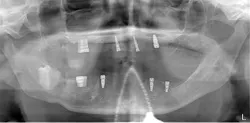

After the fabrication of full upper and lower immediate dentures, the patient underwent extraction of the remaining teeth and the placement of eight immediate dental implants (Hahn Tapered Implants, Glidewell; figure 8).

At the time of placement, ISQ readings were taken. Though the primary stability was high in these implants, the decision to allow them to integrate prior to loading was made, as each individual implant would be subjected to forces and they were not splinted. After insertion, 3-mm healing abutments were placed on all the implants except tooth No. 3, as that implant had a much lower initial stability reading. On the lower arch, 3 mm healing abutments were placed on all implants except for No. 22 due to stability. The dentures were relieved and delivered to the patient.

At one month, ISQ readings were taken of all the implants except No. 3. The lower arch showed the soft tissue healing at that time (figure 9). At 2.5 months, readings were taken again, and it was indicated that the mandibular arch had integrated and was ready for final attachment via locator attachments (Zest; figures 10 and 11). The maxillary implants were continuing to show progress, but not to the point where predictable loading was possible. Because the maxillary denture was stable (as most are), this was not an issue. The patient greatly appreciated the completion of the mandibular overdenture, which was very mobile and bothersome.

Figure 8: Post-op panorex